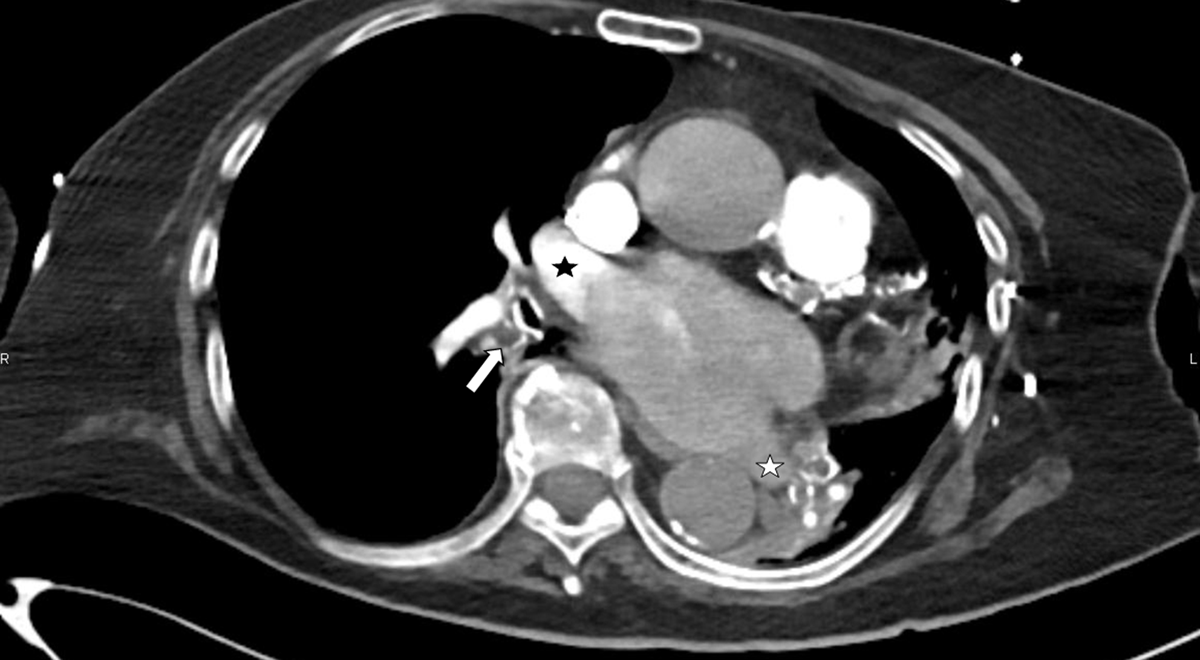

Figure 2

Axial CT of the pulmonary trunk in mediastinal window. Central bronchi on the left side are outlined by calcifications of bronchial walls cartilage and are filled with mucous (white arrow). The left superior pulmonary vein is not opacified (star). The pulmonary trunk diameter is 38.9 mm (normal being ≤27 mm in females), likely because of PA hypertension.